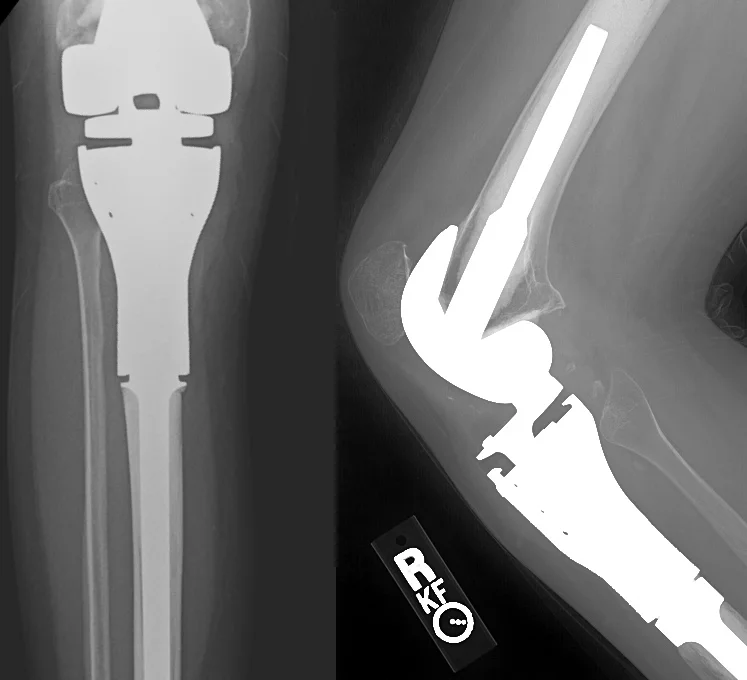

Once the bone is removed, a "trial" implant is assembled to match the size of the removed portion of tibia (first image below). This is tested inside the patient for correct fit. Then, the actual implant is assembled and inserted into the both the femur and tibia (second picture).

When reconstructing the proximal tibia, it is critical that the thigh muscles (quadriceps) are reconnected to the proximal tibia so that the patient can actively extend the knee and walk properly. Since the original tendon connection is removed along with the tibia, we use a portion of the calf muscles ("medial gastrocnemius") to bridge the two areas (third picture below). The final X-ray is shown on the right.